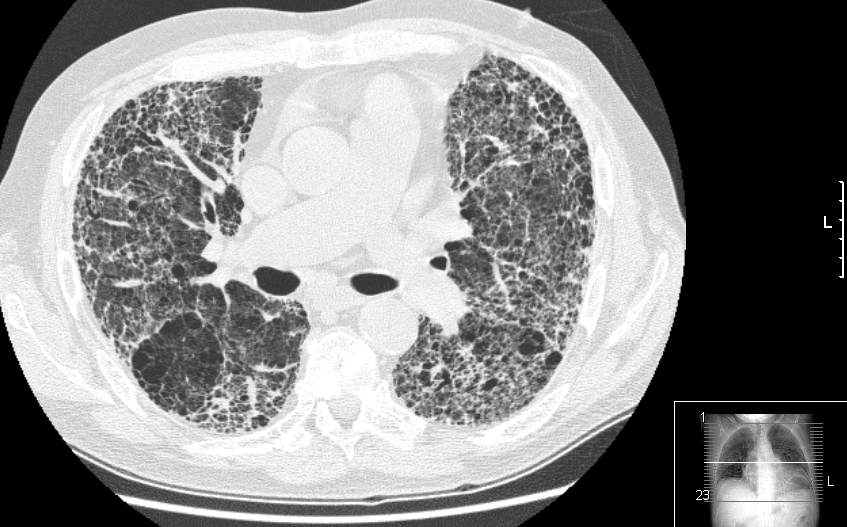

Descenso sostenido de la mortalidad por cáncer de pulmón en EEUU

La mejora se debe a una disminución de la incidencia de todos los tipos histológicos junto con un aumento en la sobrevida de los cánceres de células no pequeñas, atribuido a ls nuevas terapias dirigidas. New England Journal of Medicine, 13 de agosto de 2020.